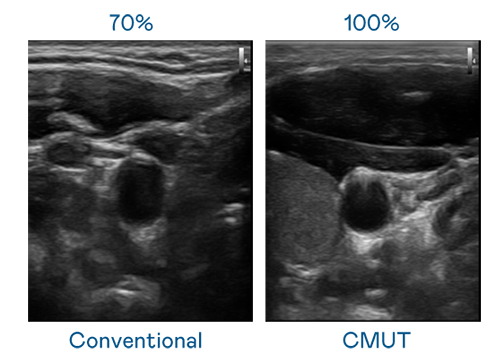

CMUT 技术是一种用电容式微机电元件来产生超音波讯号的技术。与传统 PZT 压电式技术相比,CMUT 频宽增加 30%,更宽频的超音波讯号让影像解析度大幅提升,是实现高影像品质医疗超音波扫描、促进精准医疗发展的关键技术。

大频宽带来超清晰影像

超音波影像的解析度高低,首先取决于探头能发出的讯号频宽。Ebpay CMUT 可提供高清晰的超音波讯号,提供高频宽、高灵敏度、影像纹理细节更高的超音波影像,协助医护人员缩短影像判读时间及利用精准的医疗影像进行诊断。